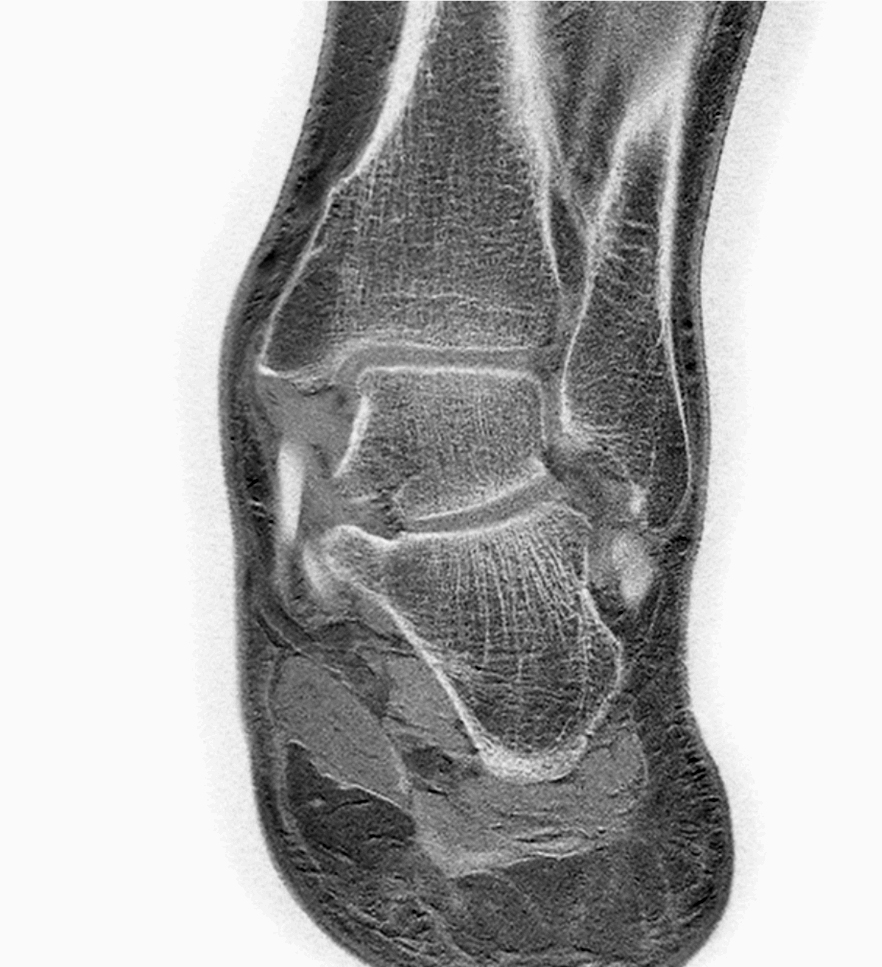

Ankle/Foot imaging post-amputation

Patient with partial amputation of the foot

Coronal T1w FFE

Coronal T1w FFE - 2 mm reformat

Coronal T1w FFE - 2 mm reformat (inverted window)